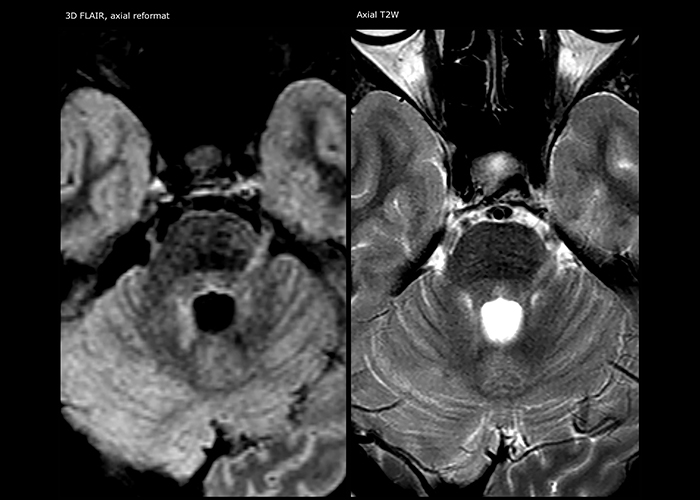

For MS imaging in the brain, Dr. Savatovsky uses 3D FLAIR as the basic sequence to visualize the lesions and assess the situation and lesion load. “We count the lesions in each location to determine if the criteria of the disease are fulfilled. We use a T2-weighted sequence because our neurologists are used to it. We compare the lesion load on FLAIR with a 3D T1 post-contrast sequence to help us determine whether lesions are old or new. We typically administer the contrast before the patient enters the machine because it shortens the examination time and allows to visualize active lesions that tend to be more visible after several minutes. When a differential diagnosis is difficult, we add sequences such as susceptibility imaging, because some focal MS lesions have a small vein in the center[3].”

“Ingenia provides great flexibility in the parameters setting. We can tune a sequence the way we want,” says Dr. Savatovsky. “For example, in a stroke exam we use a FLAIR sequence of about two minutes instead of the four-minute FLAIR we use for MS. The diffusion is 30 seconds, the T2*-weighted scan is 30 seconds, the angiography scan time is less than one minute. Ingenia is a great scanner in that situation; even with these fast sequences we can achieve good images with good SNR. When the first sequence tells us that it’s not an ischemic stroke but a hemorrhagic stroke, we may switch to a time-resolved angiography to look for vascular malformations and venous thrombosis.

“Every center is different, but for me the ideal protocol for stroke includes diffusion weighted imaging, FLAIR, and fast susceptibility imaging,” says Dr. Savatovsky. “Our fast susceptibility weighted imaging takes 50 seconds, so it’s as fast as T2*-weighted imaging. It visualizes hemorrhage but also the clots. We also do 3D MR angiography that provides information on cervical and brain vessels. If the patient does not need immediate treatment, or if additional information is needed to decide on treatment, we might also add perfusion imaging and post-contrast T1-weighted imaging.”